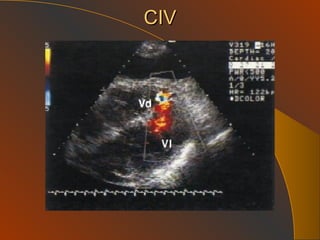

HTP Secundaria : a.  Enfermedades Cardiacas   Congenitas: CIA, CIV, Cor TriA, PDA, Ventana Ao P Adquiridas: causantes de incremento de P venas pulm. Enf Mitral severa, Enf. V.Ao. Severa,  Disfuncion VI, amiloidosis   HTP etiologia Cardiopatías y Valvulopatías izq:    Presión Auricula izq    Presión Venas Pulmonares    Presión Arteria Pulmonar

CIV

HTP Secundaria :a. Enfermedades Cardiacas Congenitas: CIA, CIV, Cor TriA, PDA, Ventana Ao P Adquiridas: causantes de incremento de P venas pulm. Enf Mitral severa, Enf. V.Ao. Severa, Disfuncion VI, amiloidosis HTP etiologia Cardiopatías y Valvulopatías izq:  Presión Auricula izq  Presión Venas Pulmonares  Presión Arteria Pulmonar